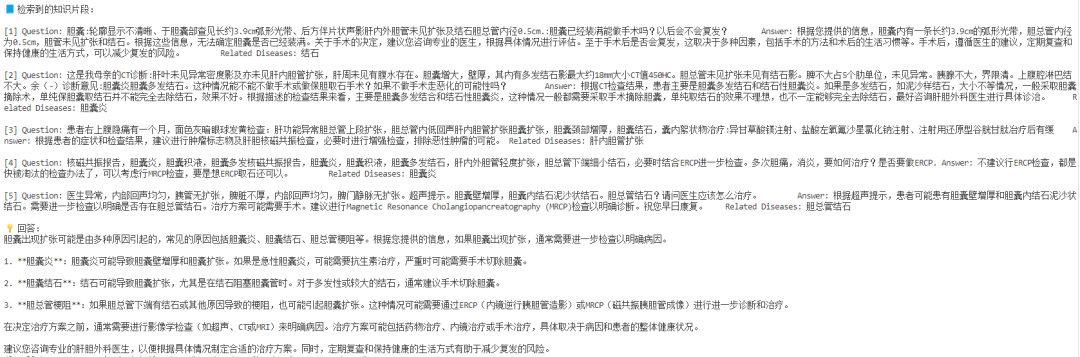

📌整理知识库——医学资料大合集

我们选用Huatuo-Lite数据集(https://huggingface.co/datasets/FreedomIntelligence/Huatuo26M-Lite ),这是目前最大的中文医疗问答数据集,这些问答对通过文本清洗和数据去重的方法,从多个来源精心收集而来,包括在线医疗咨询网站、医学百科全书和医学知识库,覆盖了广泛的医疗知识。该数据集的创建显著扩大了医疗领域问答数据集的规模,并为中文医疗领域的自然语言处理和人工智能研究提供了一个前所未有的资源。

通过如下代码,我们可以获取数据,构建知识库:

📌实现RAG——模型+知识双保险

🗝️原理:输入(用户带CT提问+微调后的VQA的初诊结果) → 向量检索相关医学知识 → 与输入拼接 → 喂给模型生成回答。

RAG 就像给模型配了「助理医生」,先去查资料,再结合自身能力回答,大大提升准确率和可信度。我们对输入的QA对进行拼接,并要求大模型根据提供的问题和CT影像的初步诊断结果,结合知识库召回结果进行回答:

📌效果展示

➡️input:下面是CT医疗问诊的问题以及CT图像初步诊断。问题:does the gallbladder appear distended?;图像初步诊断:yes;

➡️output:

可以看到小助手召回了相关片段并给出了回答!通过微调+RAG,LLM不再“闭门造车”,而是真正拥有了读万卷书 + 亲临临床的实力,成为你身边靠谱的AI医学助理!